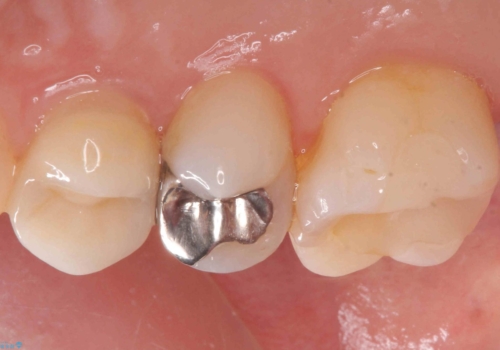

- 銀の詰め物を白くしたいとのことで来院されました。

セラミックインレーでの治療を行いました。

- 右上5 セラミックインレー 77,000円×1本費用は治療当時の料金となります